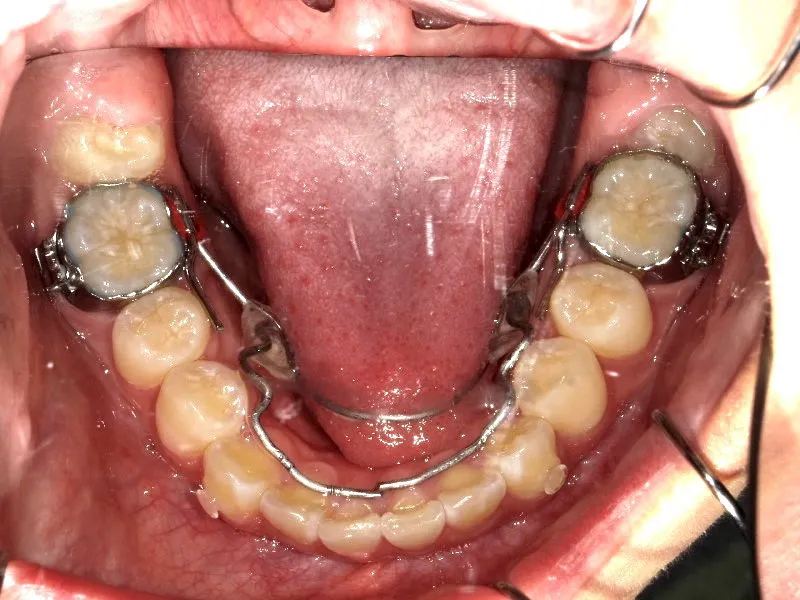

診断名 叢生 装置名

拡大床

ブラケット・

ワイヤー

付けずに治した

下の歯がずれて生えています。

こどもの歯は下の2本しか抜けていませんが、放っておくとガタガタがきつくなるので、早い段階からの治療としました。